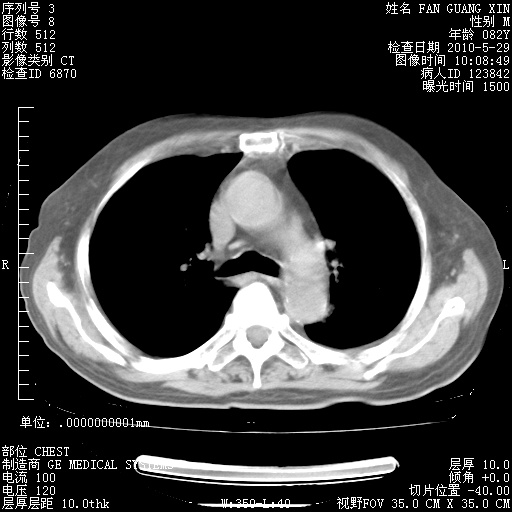

治疗3周后的肺部CT纵隔窗

再治疗10天后的肺部CT 纵膈窗

阅读此次胸部CT,肺间质渗出性改变较入院时有吸收。目前从体温、白细胞、中性分叶明显增高,肯定存在细菌感染(发生医院感染哦,若无消化道及泌尿系统等感染的依据,肺部感染可能大)。若你院头孢哌酮舒巴坦钠耐药率较高,同意你的方案,若48小时体温仍高,可考虑使用碳青霉稀类抗菌药物,同时可予超声雾化、注意滴数时加大液体量。白蛋白33.30g/L较低哦,需加强营养等支持治疗。